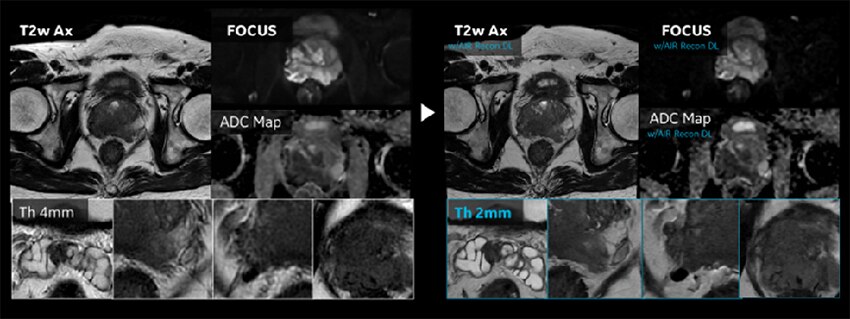

Figure. 3

前立腺プロトコルの変遷。従来より薄いスライスで撮像することにより部分容積効果を低減させて、シャープな画像を得ることが出来る。

前立腺はAIR™ Recon DLの機能が最も効果的に活用されている領域の一つで、「SNR向上」「Thin slice化」「撮像時間短縮」の3つの恩恵が効率的に得られている。特に前立腺MR診断における重要なコントラストであるT2強調像と拡散強調像の画質向上効果の恩恵が大きい。

従来の前立腺のT2強調像プロトコルは、PI-RADSに準拠してスライス厚3mmで行っていたが、AIR Recon DLの導入により2mmで行っている。従来のシステムでPI-RADSに準拠したプロトコルを設定した場合、十分なSNRを得るためには時間をかけて撮像を行う必要があったが、AIR™ Recon DL導入システムでは2mmで撮像を行ってもSNRが十分に保たれた画像を、2分台で得ることが出来る(Figure.3)。部分容積効果の低減により前立腺のコントラストが明瞭になり、淡い信号領域内の低信号域が検出され、臨床的価値の高い画像が提供される。さらに前立腺がんの被膜外進展の検出にも有効で、脂肪織への浸潤などの同定に有用である。AIR™ IQ Editionによる画質向上によって微細な構造が見えるようになり、診断の信頼性が向上していると感じている。